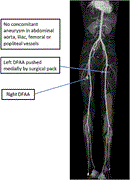

Simultaneous bilateral deep femoral artery aneurysms: case report of a rare peripheral arterial aneurysm

Rahel Abebayehu Assefa and others

Journal of Surgical Case Reports, Volume 2025, Issue 1, January 2025, rjae821, https://doi.org/10.1093/jscr/rjae821